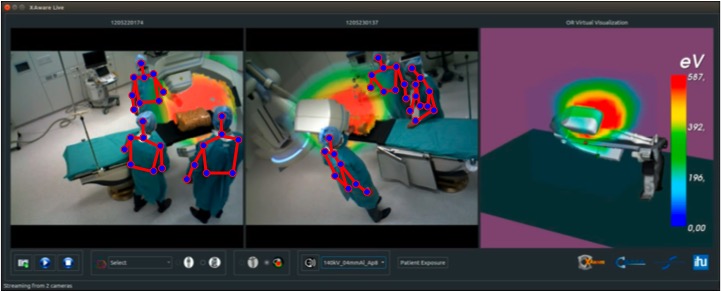

An essential component of the control tower is the data-driven modeling and understanding of the clinical activities, an undertaking that taps into the emerging research field of Surgical Data Science [3, 4]. Machine learning has been key to generate models of procedural interventions from data [139, 140] and ontologies have also been developed to standardize the resulting models [141]. Implementations of such AI-based applications start to emerge in various institutions, besides the ones focusing on analysing endoscopic videos already mentioned in Section V. As video data remains one of the main source of information, they highly rely on deep learning. Videos captured by cameras mounted in the room provide indeed a rich source of information about the activities without disrupting the workflow. For instance, a patient and staff radiation exposure monitoring system for hybrid procedures illustrated in Figure 4 was proposed in [134]. It relies on several RGB-D cameras to estimate the 3D pose of the persons and room layout, which can then be used to simulate and visualize in situ X-ray propagation around the patient table. [142] develops a system to monitor hand-hygiene in hospital corridors in order to analyse and reduce hospital acquired infection. The approach uses a large set of depth cameras installed to observe the hand-soap dispensers. For the intensive care unit, [143, 144] present methods based on color or depth video data for the detection of patient mobilization activities. Key building blocks to the success of these applications are the estimation of clinician and staff poses [145, 146, 147], as well as the recognition of their activities [148, 149, 150, 151]. As for traditional visual data, deep learning based approaches are currently the best performing methods for these tasks, though it should be noted that they do not necessarily perform as well on clinical data yet. This is due to the specificity of clinical videos, where staff wear gowns and masks, colors are often similar, and cameras observe the room from restricted positions, but also from the fact that there is no clinical COCO or Imagenet dataset yet. [152] evaluates state-of-the-art human pose estimation approaches and [153] state-of-the-art face detection approaches on clinical data. Both studies show a large margin for improvement. Since the development of large annotated datasets of clinical videos may be difficult due to the expertise required and the restrictions on data, other approaches need to be developed, for instance using non annotated data for transfer learning [153].